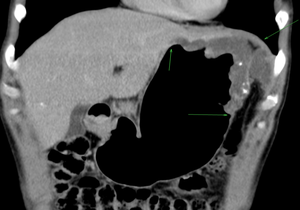

КТ-пневмогастрография – уникальный метод визуализации минимальных опухолей желудка при компьютерной томографии, основанный на раздувании желудка (газообразующей смесью). На выполнение этой методики получен патент сотрудником нашего отделения.